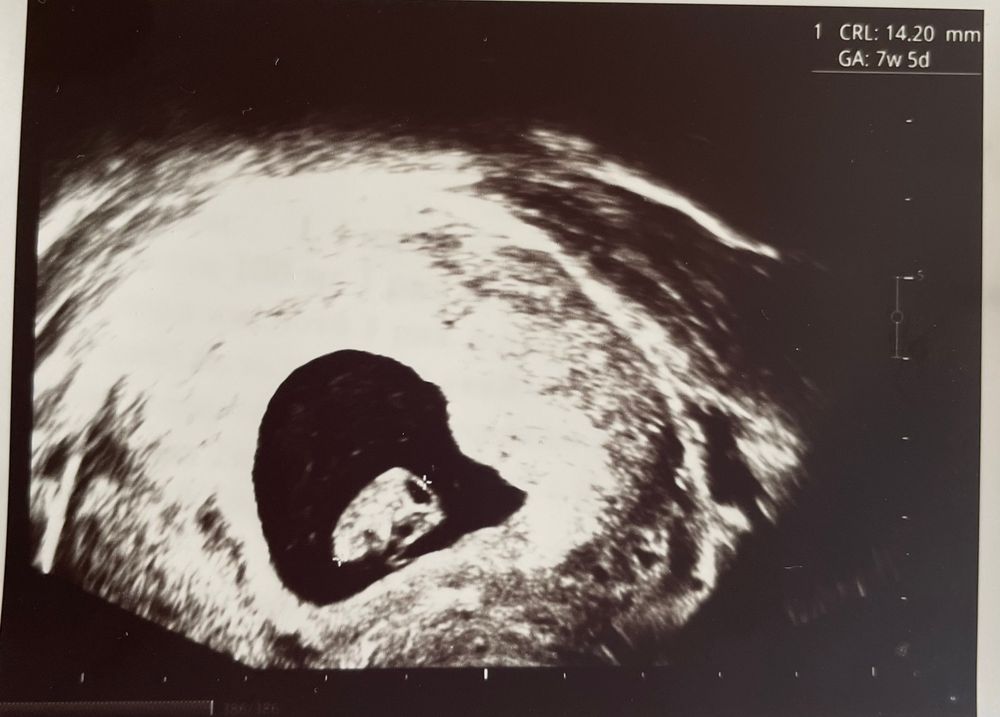

34 дпп узи

Я БЕРЕМЕННА !Были сегодня на узи вместе с мужем. 14 мм человек, чуть опережает срок - 7 недель 5 дней поставили. Сердце бьется как паровоз, так интересно видеть как оно пульсирует на экране. Нашли небольшую гематому, но сказали не переживать из-за нее, она ниже места прикрепления.